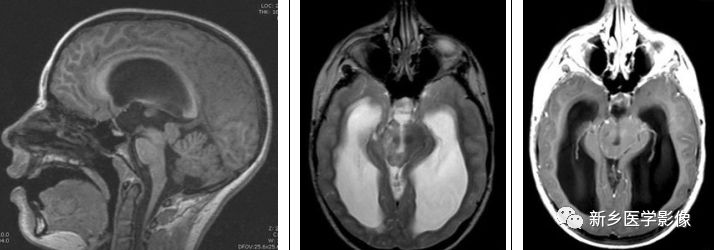

颅内表皮样肿瘤为先天性肿瘤,约占颅内肿瘤的1%。其通常发生于脑基底池及脑室,尤其是桥小脑角,鞍旁及第四脑室。它们进入脑脊液空间,产生明显肿块占位效应。在常规MRI上,它们的信号与脑脊液类似,有时,可表现为“脏脑脊液”表现。DWI是鉴别表皮样肿瘤与蛛网膜囊肿的有效方法,通过表观弥散系数反映了表皮样瘤内部的固体性质,而蛛网膜囊肿为纯液。

矢状位及横断位T1WI示松果体区一混杂、高信号肿块,横断位T2WI及FLAIR呈高信号,横断位及矢状位T1WI+C未见明显强化,DWI示呈高信号,符合弥散受限。